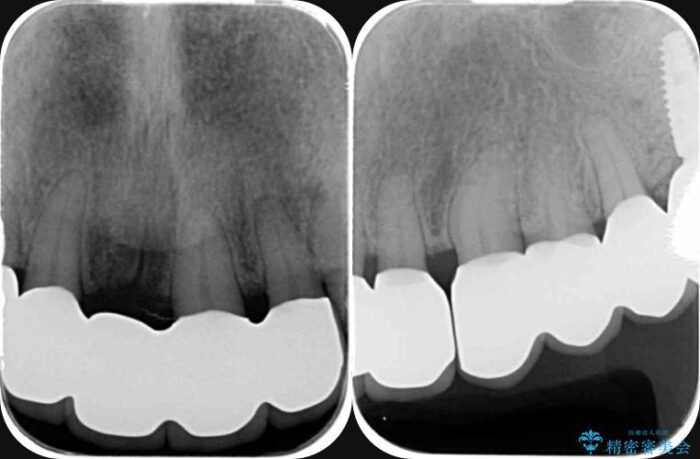

治療後について

歯周病によって失われた歯を支える骨(歯槽骨)に対し、再生療法を用いることで骨の再生・回復を実現しました。骨の高さが改善されたことで、歯の土台が強化され、将来にわたって歯をしっかりと支え続けられる口腔内環境を整えることができました。